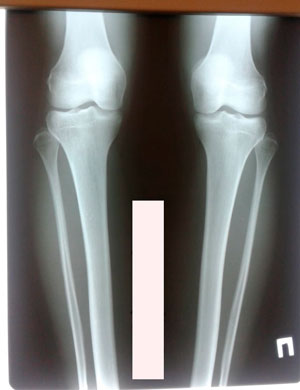

Диагноз: варусная деформация голеней. Ротация с обеих сторон.